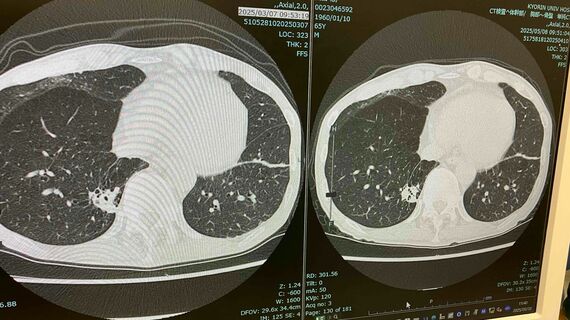

最大のポイントはCT画像である。主治医が目の前のパソコンを操作し、モニターに腫瘍が転移した肺の画面を大きく映し出して説明し始めた。

「左が3月、右が今回の画面です。左画像の左側にある星雲状の腫瘍が、右画像ではくっきりとした形になっています。そして左画像の右下にある楕円形の腫瘍が5月のほうが若干大きめで鮮明になっています。ただ、痰が集積してこういう状態に見えることもあり、腫瘍が大きくなったとは言い切れません」

一見、がん細胞の活動が活発化して腫瘍が大きくなったかのように思えるが、必ずしもそうとは言い切れないとのことだ。病巣が進行していないのではないかということは、次の画像からも明らかだった。

「先ほどよりも肺の下を映した画像です。画面の左右の小さな腫瘍は今回、明らかに小さくなっています。左側中央部近くにある楕円形の腫瘍もやはり小さくなっています。そしてもう一カ所。腰骨の部分ですが、ここは今回も、転移しているのかどうかはっきりしないほどモヤモヤした状態です」

1月から3月にかけてはだれが見ても明らかなほど腫瘍が縮小していたが、今回はがん細胞の増殖活動による肥大化は見られず、一部は縮小化。全体的に進行は抑えられているといった状況だった。その結果、主治医の判定は「不変」ということになった。